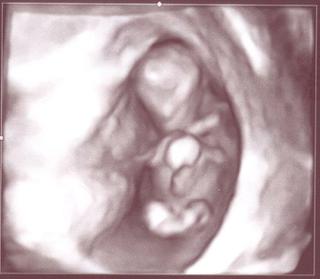

Jinak jsme dopadli dobře, když jsem to naše miminečko viděla, tak se mi začlo chtít brečet... když mi ho doktor ukázal, tak zrovna pěkně mávalo ručičkou a i kopalo nožičkama.. no krásný.. vydyndala jsem snímek a další bude až za hoooodně dlouho..